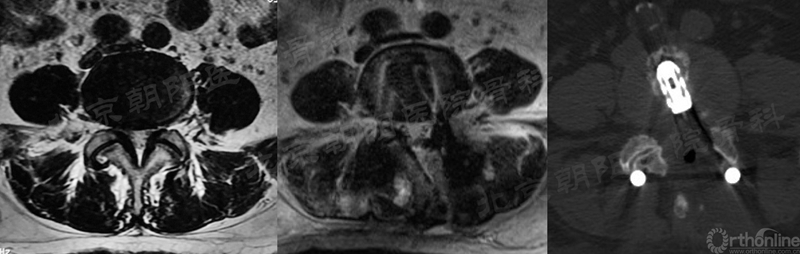

术前MRI和术中定位

术前、术后MRI及CT(轴位)